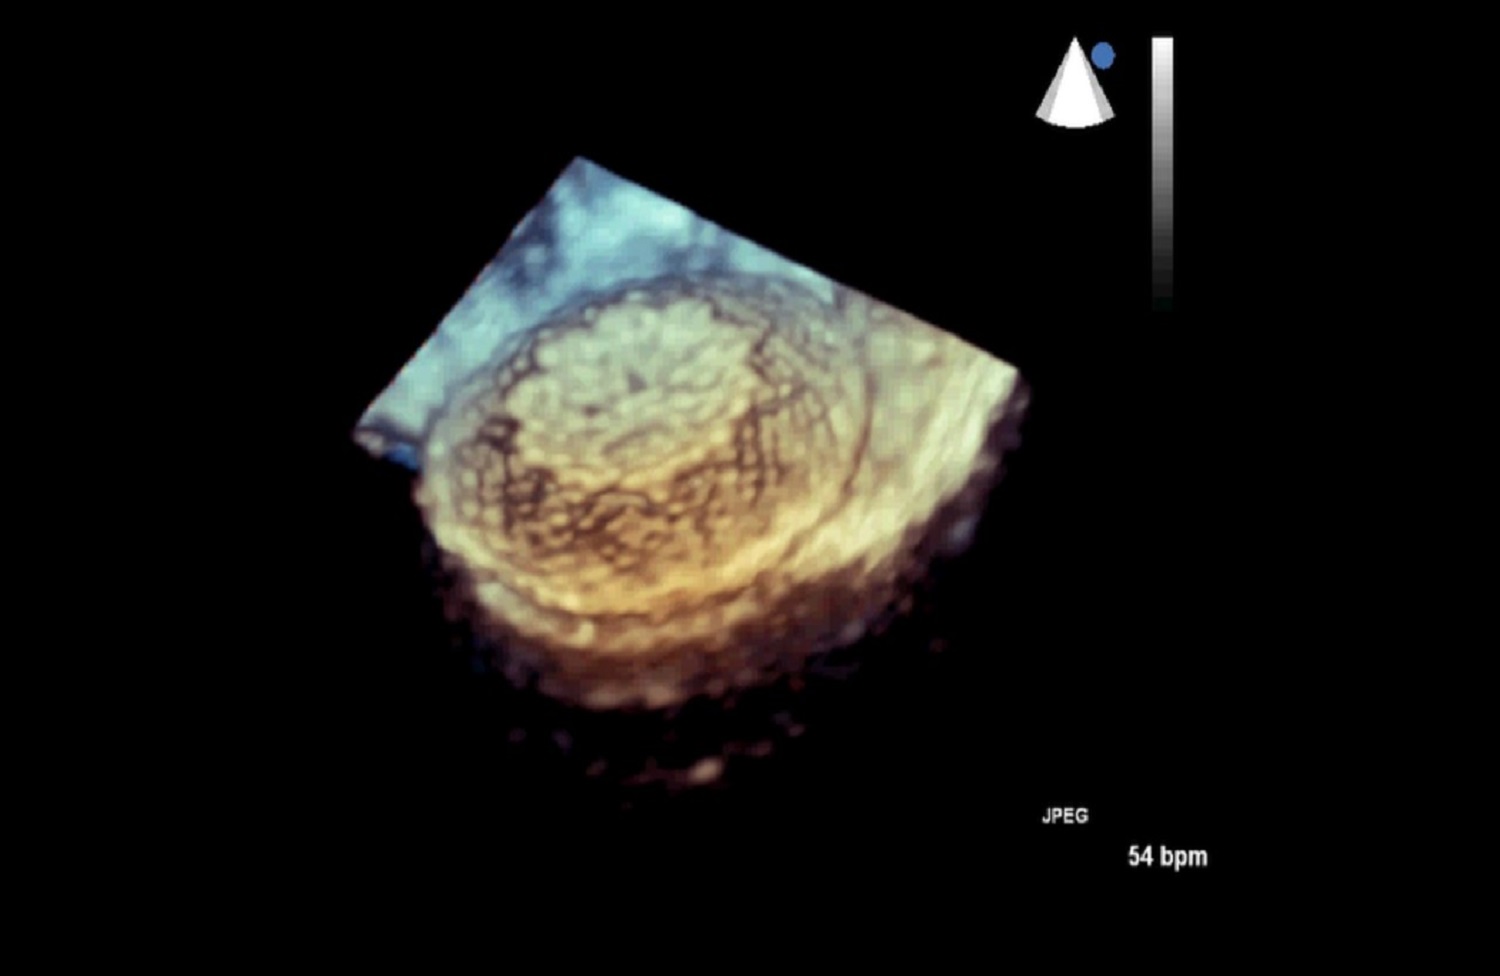

Pracownia Echokardiograficzna Kliniki posiada Akredytację Klasy C (najwyższy poziom referencyjny) przyznaną przez Zarząd Sekcji Echokardiografii Polskiego Towarzystwa Kardiologicznego. W ciągu roku wykonywanych jest tu łącznie ponad 3600 badań echokardiograficznych przezklatkowych, przezprzełykowych i prób z dobutaminą.

Pracownia wyposażona jest w 2 aparaty przenośne: Philips CX 50 oraz Vivid Q.

W Pracowni badani są pacjenci hospitalizowani w oddziałach Kliniki oraz we wszystkich pozostałych Klinikach Szpitala Klinicznego Dzieciątka Jezus, a także pacjenci ambulatoryjni kierowani z Poradni Kardiologicznej, Nadciśnienia Tętniczego, Przeciwzakrzepowej, Transplantacyjnej i Nefrologicznej Szpitala. Pracownia ukierunkowana jest na diagnostykę zatorowości płucnej, nadciśnienia płucnego, wad zastawkowych, infekcyjnego zapalenia wsierdzia oraz dysfunkcji lewej komory.

Dzięki wykwalifikowanemu personelowi i nowoczesnemu sprzętowi w Klinice wykonywane są również przezskórne zabiegi zamknięcia ubytków przegrody międzyprzedsionkowej typu II oraz drożnego otworu owalnego, pod kontrolą echokardiografii dwu – i trójwymiarowej.

Na podstawie badań z zastosowaniem przezprzełykowej echokardiografii trójwymiarowej w pracowni kwalifikuje się również pacjentów z ciężką niedomykalnością mitralną w mechanizmie wypadania płatka mitralnego do nowatorskich zabiegów małoinwazyjnej przezkoniuszkowej naprawy zastawki bez użycia krążenia pozaustrojowego. Efektem współpracy z Oddziałem Kardiochirurgii Szpitala Medicover była możliwość monitorowania echokardiograficznego przezprzełykowego dwóch pierwszych w Polsce zabiegów naprawy zastawki mitralnej z użyciem robota chirurgicznego da Vinci.

Działalność Pracowni jest dynamiczna – realizowane są tu programy naukowe dotyczące chorych z zatorowością płucną, zakrzepowo-zatorowym nadciśnieniem płucnym, twardziną układową, toczniem układowym, otyłością olbrzymią, u pacjentów przed i po przeszczepieniu narządów (wątroby, nerek, trzustki) oraz z dystrofiami mięśniowymi. Członkowie Zespołu prezentują wyniki prowadzonych obserwacji na zjazdach Sekcji Echokardiografii PTK i oraz kongresach za granicą, m.in. EuroECHO.